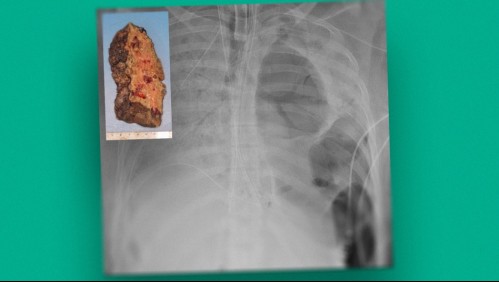

Calidad de vida Así quedó el pulmón de una paciente contagiada con coronavirus: Tuvo que ser trasplantada